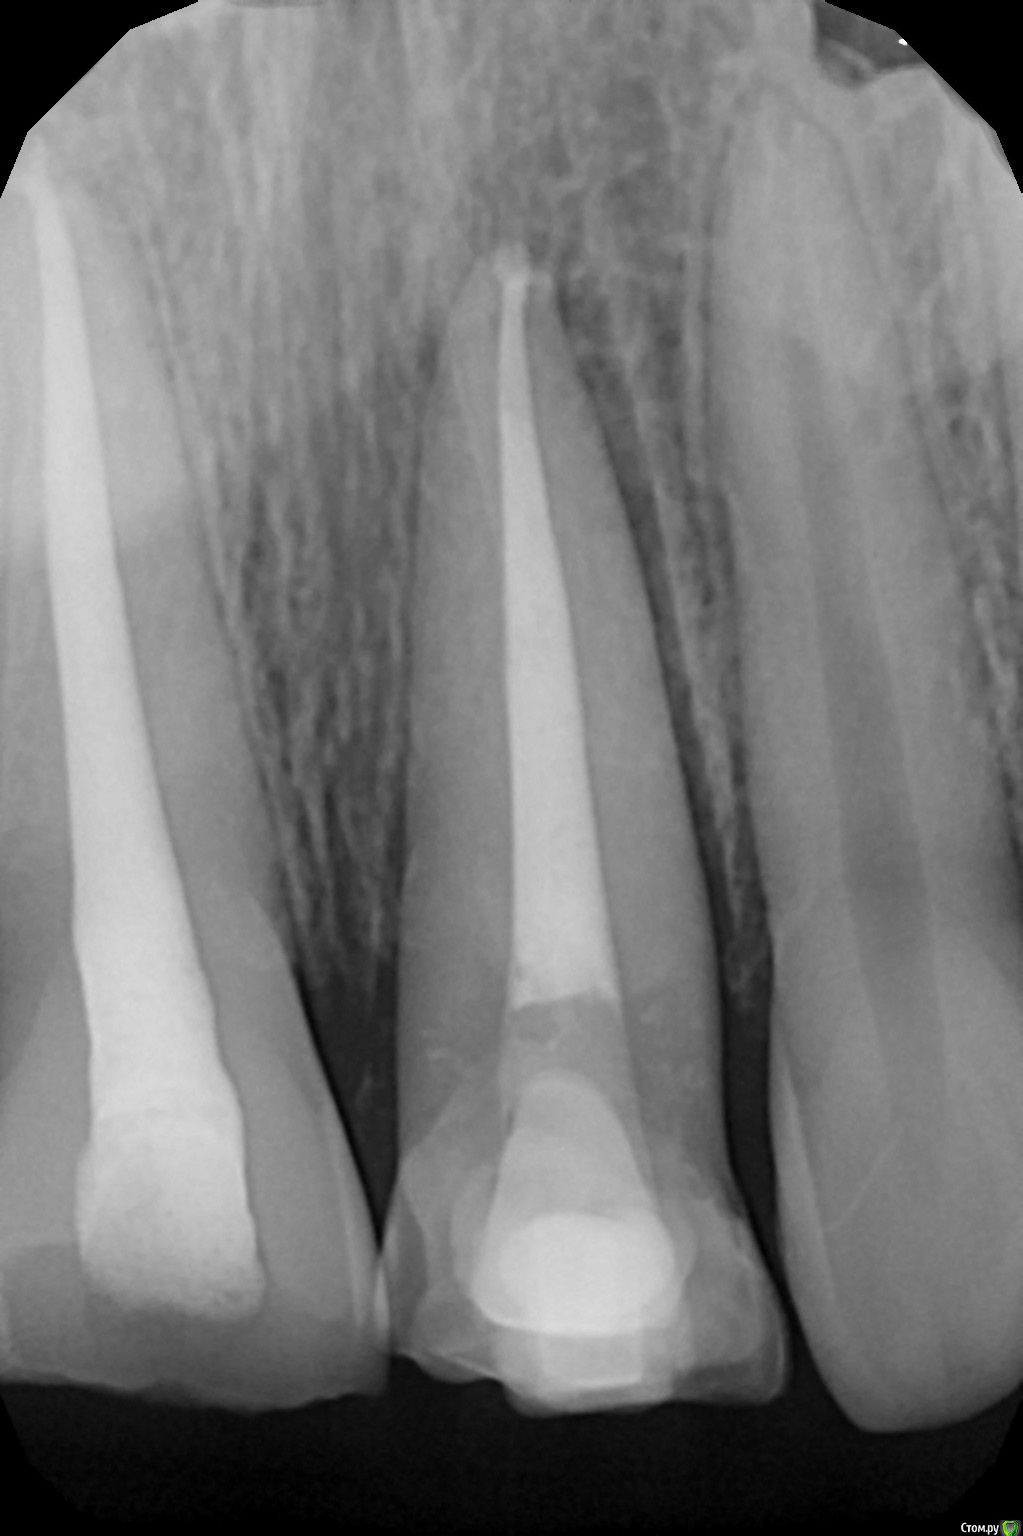

Art 7 Опубликовано 11 августа, 2017 Поделиться Опубликовано 11 августа, 2017 ставишь стекловолоконную балку между апроксимальных поверхностях соседних зубов) Ссылка на комментарий

kamranchick Опубликовано 11 августа, 2017 Автор Поделиться Опубликовано 11 августа, 2017 ставишь стекловолоконную балку между апроксимальных поверхностях соседних зубов)Спасибо Артурчик)Попробуем так))) просто шатается сильно, страшно трогать пока что) Ссылка на комментарий

1586Doc Опубликовано 11 августа, 2017 Поделиться Опубликовано 11 августа, 2017 (изменено) Это обычная силиконовая каппа ?вытягиваем, потом стабилизация ? Как на долго? Изменено 11 августа, 2017 пользователем 1586Doc Ссылка на комментарий

kamranchick Опубликовано 11 августа, 2017 Автор Поделиться Опубликовано 11 августа, 2017 Это обычная силиконовая каппа ?вытягиваем, потом стабилизация ? Как на долго?капу сделали вакуум формером, помоему она пластмассовая вроде. стабилизация 2-3 месяца... Ссылка на комментарий